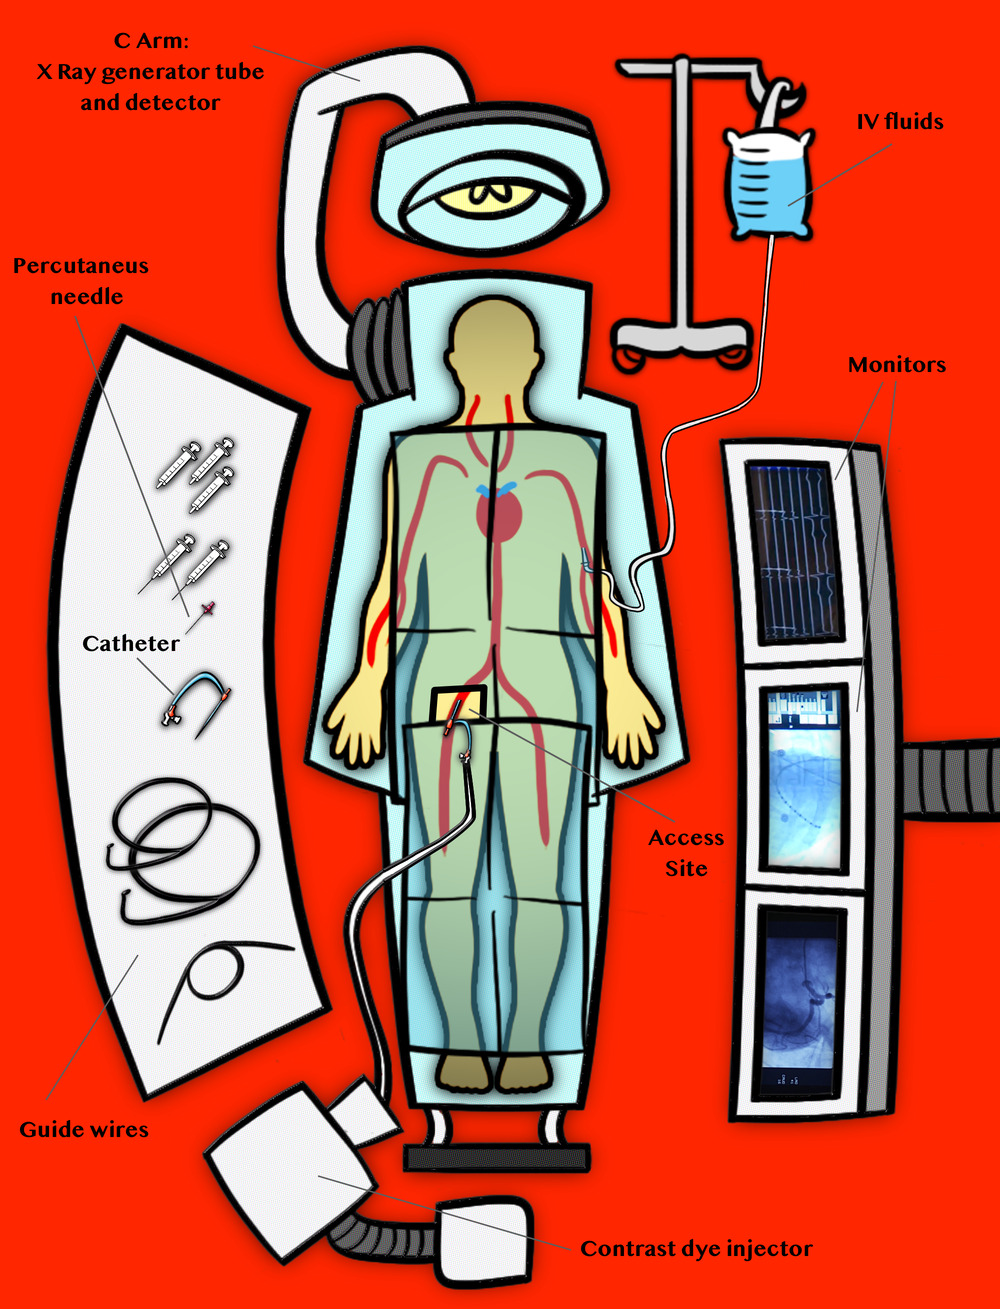

The term catheterization comes from the word catheter. The catheter is the plastic tube used during the procedure to let tools reach inside the patient’s body. Catheterization is different from standard surgery, where doctors cut the skin with a scalpel for access to the body. In a catheterization, everything happens through a small incision made with a needle.

Cardiac catheterizations are part of a group of procedures called "minimally invasive". Minimally invasive procedures offer a much smaller risk of infection and a quicker recovery than classic surgery. Cardiac caths do not involve general anesthesia, so the patient is not put to sleep. Instead, they are done under sedation and local anesthesia. The patient stays awake, but is given medication to help stay calm and comfortable. Then local anesthesia is injected under the skin where the catheter will enter the body. The technology in cardiac caths was invented in the 1940s, and caths have been done routinely since the 1980s. Cardiac caths are done by a sub-specialist known as an invasive cardiologist, and performed in a special operating room-like facility called a catheterization laboratory. Today, over one million are done in the United States every year.

The day before the cath, a nurse will call you and review the medication you take. She will also tell you what to take the day of the procedure. When you arrive for the cath, the lab staff will set you up on the cath table, hook you up to the heart monitor and make sure your IV is working. You will receive medication that will help you relax and maybe even sleep during the cath. But don’t be surprised if you stay awake, as this is not unusual. The site where the catheter will be placed is then numbed. This is done by injecting medication around the area with a syringe. Once the area is numbed, a needle will be used to reach one of your arteries. Once the needle is inside the artery, it will be replaced with a sheath. The sheath will be the main portal into your body. Everything the doctor needs to study and treat your heart will enter through the sheath. The catheter is inserted next. It will travel through the arteries of your body to your heart, all through that same little incision.